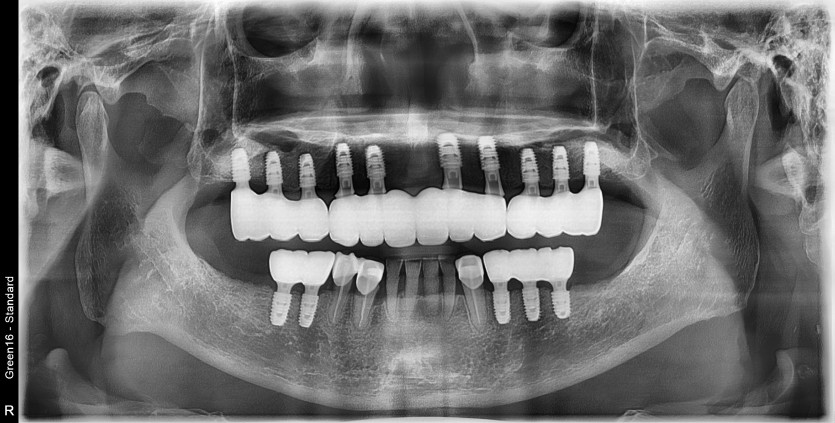

만 68세 상악 전체 임플란트 증례(하악 일부)

상악 전체 임플란트 증례입니다.(하악 일부)

15개의 임플란트로 완성하였습니다.